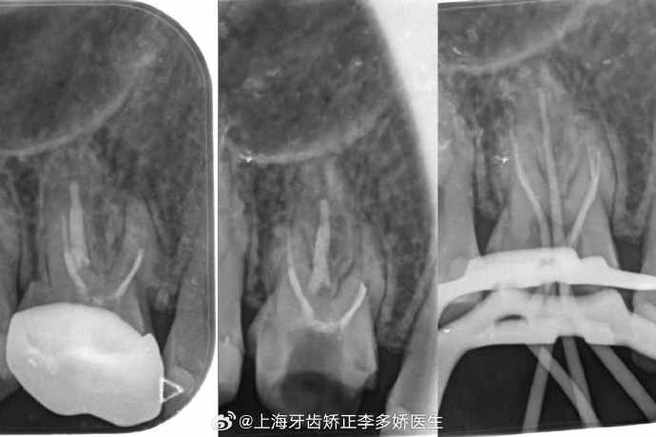

(图片来源网络,侵删)